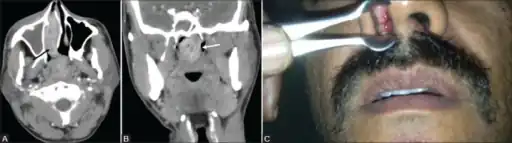

Contrast-enhanced CT PNS a) Axial image shows an enhancing soft tissue lesion (black arrow) in the right inferior nasal cavity extending through the choana into the nasopharynx. b) Coronal section shows lobulated nasopharyngeal extension of the lesion (white arrow) with prominent leash of blood vessels. c) Anterior rhinoscopy shows a red fleshy mass with whitish spots in the right nasal cavity. Diagnosis after surgery confirmed as rhinosporidiosis